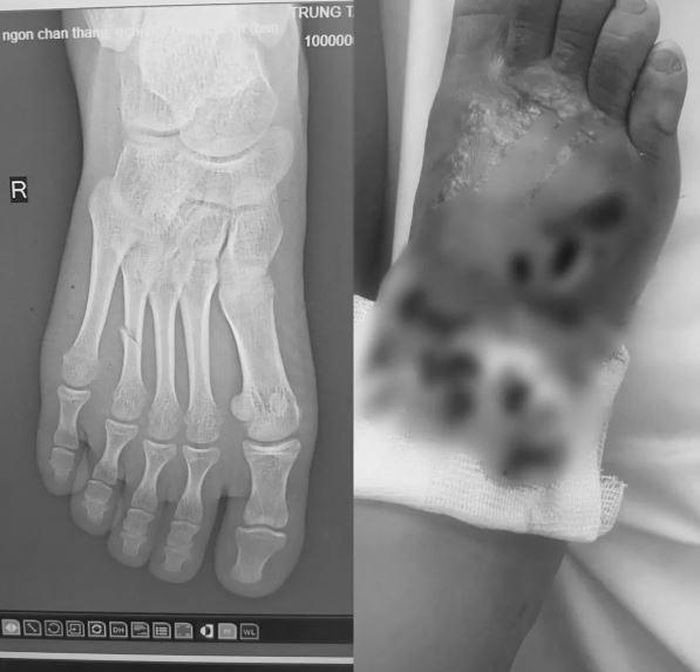

Bệnh nhi 14 tuổi bị gãy xương đốt bàn chân kèm nhiễm trùng nặng. Ảnh: BVCC.

Theo lời người nhà, khoảng 2 tuần trước, bệnh nhi bị ngã và gãy chân. Thay vì đưa con đến cơ sở y tế, gia đình đã lựa chọn điều trị bằng cách bó thuốc nam theo phương pháp dân gian.

Chỉ sau 5 ngày, chân cháu sưng to, đau nhức liên tục, xuất hiện mủ có mùi hôi. Khi các triệu chứng ngày càng nặng, gia đình mới đưa cháu tới Trung tâm Y tế huyện Đoan Hùng.

Tại đây, kết quả chụp X-quang cho thấy bệnh nhi bị gãy xương đốt bàn chân, kèm theo nhiễm trùng mô mềm nặng. Các bác sĩ đã tiến hành điều trị kháng sinh liều cao, làm sạch ổ hoại tử và bó bột hở vùng tổn thương. Sau 1 tuần điều trị tích cực, tình trạng nhiễm trùng đã cải thiện, sức khỏe bệnh nhi dần ổn định.